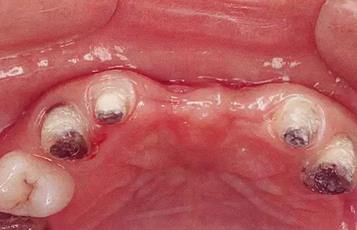

360截圖20170422101920025.jpg

▲圖7-2,3

▲圖7-2 齦瓣剝離后,可以看到右上3近中側(cè)沉積著大量牙結(jié)石。由于牙根接近而無法用刮匙除去

▲圖7-3  牙周外科處理后的愈合期狀態(tài)。右上2,3之間愈合形成了充分的角化齦。